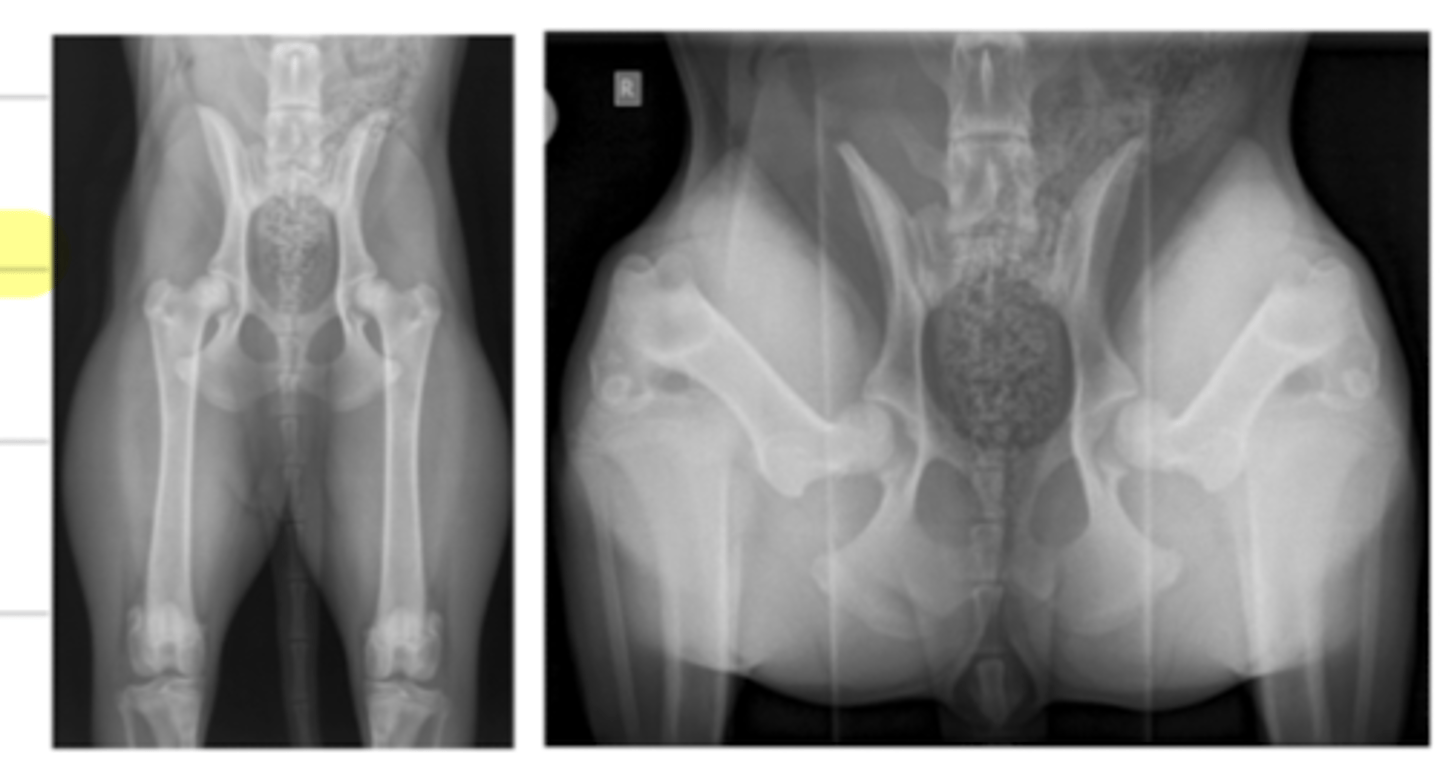

what are the 5 opacities of a radiograph, from most radioluscent to most radiopaque?

1. air

2. fat

3. soft tissue and fluid

4. mineral (bone)

5. metal

what are the 5 opacities of a radiograph?